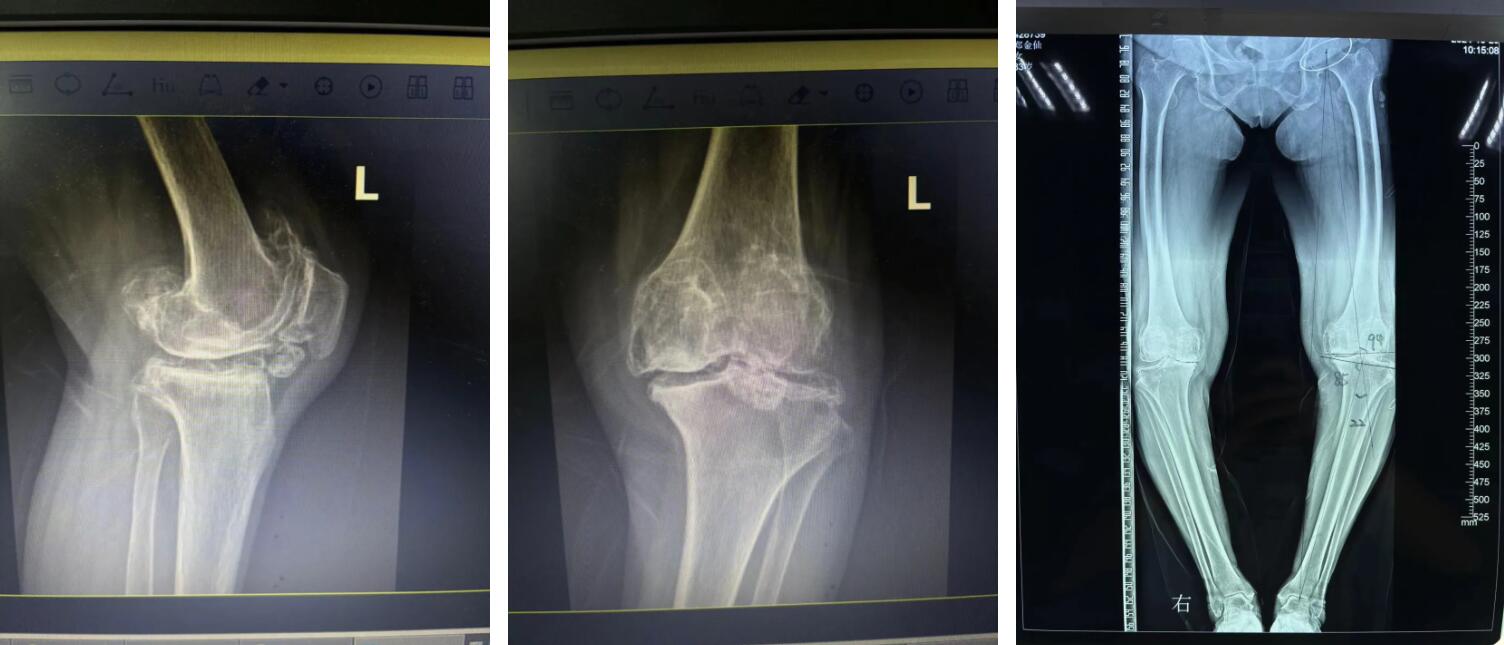

10月,一個秋高氣爽的好季節(jié),84歲,一個安享晚年的幸福時期,但對于正處在這個階段的鄭阿婆來說卻日日痛苦不堪、滿面愁容,原來是鄭阿婆的雙腿因長年疼痛難忍無法正常下地行走,期間也輾轉治療于多家醫(yī)院,但始終無法恢復,久而久之輪椅便成了阿婆的唯一依靠。

可是現(xiàn)如今阿婆雙膝部的疼痛逐漸加重,膝蓋也嚴重變形,終日苦不堪言,家里兒女看到后甚是心疼,最終經過多方打聽后,鄭阿婆在家人的陪同下來到廣安醫(yī)院找到了關節(jié)科羅軍副院長。

羅院長仔細了解鄭阿婆的病情后,第一時間為阿婆確定了左側人工全膝關節(jié)置換手術的治療方向,并制定了詳細的治療方案,最終得到了阿婆和家屬的一致認同。

住院后,羅院長立即給阿婆安排一對一術前規(guī)劃、術前3D打印,做到了關節(jié)置換的“量身定制”,最終在羅軍手術團隊的努力下阿婆順利完成了機器人輔助下左側人工全膝關節(jié)置換手術治療。